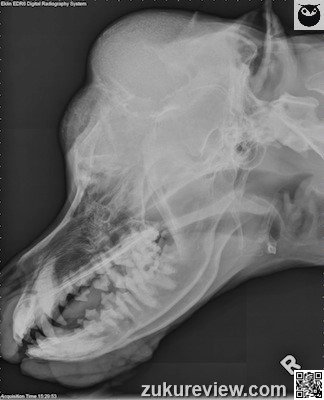

The top differential diagnoses of this skull tumor are osteosarcoma (OSA), chondrosarcoma (CSA), and multilobular osteochondrosarcoma (MLO).

OSA is the most common primary bone tumor of dogs and skull OSA accounts for < 3% of all OSA. Axial OSA carries a more favorable prognosis than appendicular OSA, and Tx consists of radiation and chemotherapy.

Chondrosarcoma is a malignant, cartilage-producing tumor, and the second-most common primary bone tumor. Unlike OSA, CSA is more common in the axial skeleton than appendicular skeleton. Surgery is the Tx of choice for CSA, with radiation therapy recommended for unresectable tumors.

MLO presents as a firm, fixed mass arising from the periosteum. Clinical signs are referable to location. Tx is surgical with unknown effects of chemotherapy and radiation.